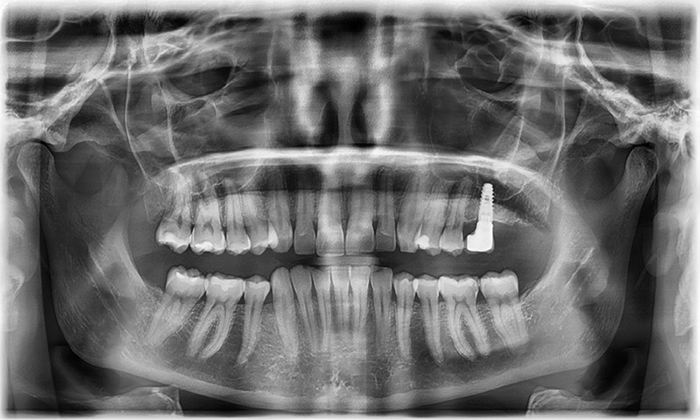

Upon examination, her left central incisor was slightly larger than the right, and there was mild crowding in both upper and lower anterior teeth. She had previously undergone extraction orthodontics—her lower first premolars had been removed, leaving a small gap on the right side. In addition, due to deep overbite, her lower front teeth were barely visible. She also had a dental implant on her lower left first molar, while the second molar was missing.